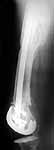

TAC> I can't actually see the osteotomy on either radiograph. Is it more proximal than we see in these radiographs or so well aligned as to be not visible?

The osteotomy was performed through the fracture site. See the attachment.